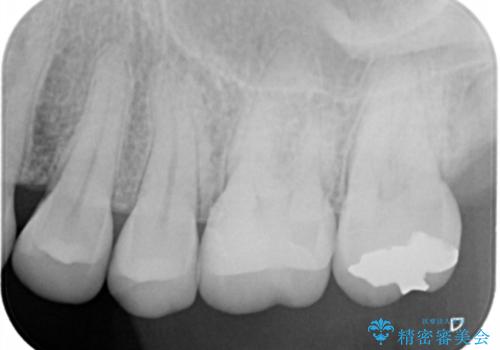

- 左上6番の銀歯をセラミックにしたいと希望され来院された患者様です。

切削量を考慮し、セラミックインレーを選択しました。

銀歯を除去したところ虫歯が深かったので、CRを詰めた上で形態を整えています。